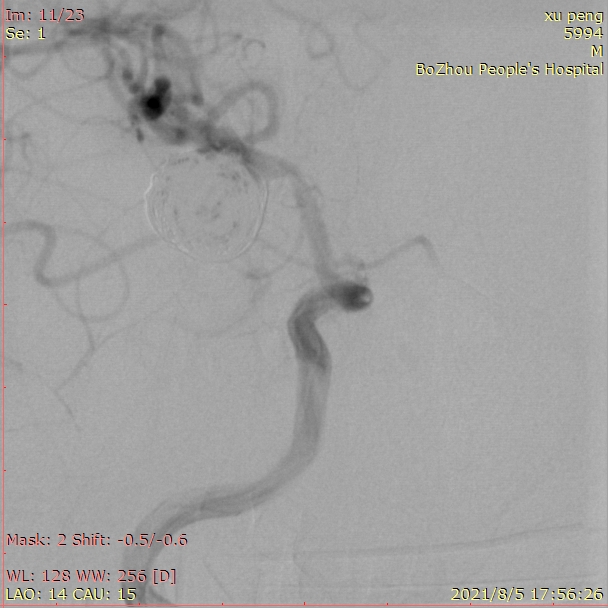

观察15分钟后再次造影,正位片。

观察15分钟后再次造影,侧位片。

载瘤动脉通畅,手术结束。

术后患者带气管插管回病房,次日病人神志清楚,四肢活动自如。